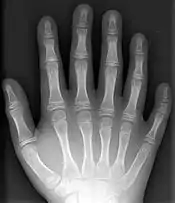

پُرانگشتی یا پلیداکتیلی (به انگلیسی: Polydactyly) نوعی بیماری مادرزادی است که در آن فرد بیمار بیش از پنج انگشت در هر دست یا پا دارد. این بیماری از شایعترین بیماریهای مادرزادی است. به طور میانگین در هر ۵۰۰ نوزاد متولد شده٫ ۱ نوزاد مبتلا به پلی داکتیلی است. پلی داکتیلی به شکلهای گوناگونی ظاهر میشود. ممکن است این بیماری با دیگر ناهنجاریهای مادرزادی مانند بیماریهای قلبی و خونی همراه باشد.

| دست چپ یک بیمار مبتلا به پلی داکتیلی | |

انگشت اضافه در بیشتر موارد کنار انگشت کوچک دست رو به بیرون قرار دارد. در بعضی موارد انگشت اضافه در طرف انگشت شست است. به ندرت اتفاق میافتد که انگشت اضافه بین انگشتان میانی قرار داشته باشد.

انگشت اضافه به شکلهای متفاوتی ظاهر میشود. این انگشت میتواند پوستی یا گوشتی باشد؛ و حتی یک یا چند بند استخوانی داشته باشد. در بعضی موارد استخوانهای آن به استخوانهای کف دست متصل است. گاهی انگشت در انتها دو شاخه میشود و دو انگشت به وجود میآورد.